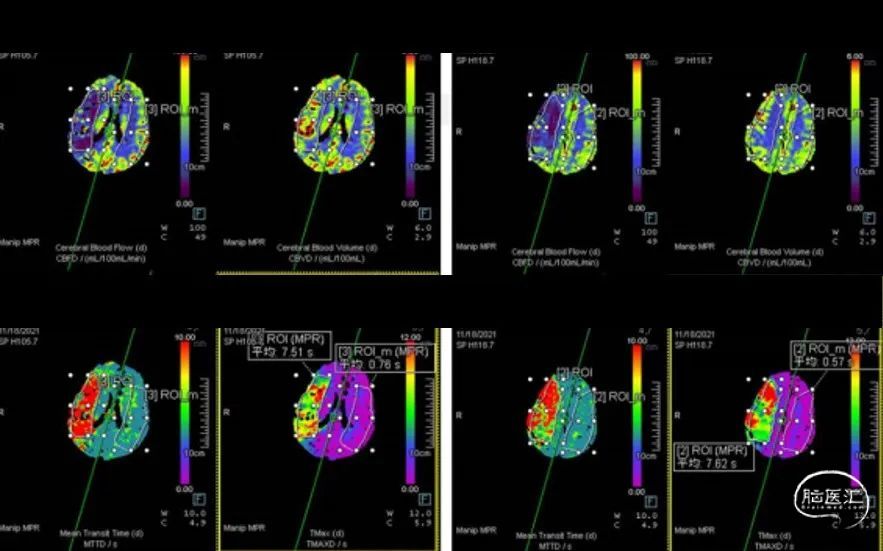

术前头颅CTP:

1. 头颅CTP原始数据提示累及M1分叉的小负荷血栓团块。

2. CTP定量测定半暗带大小。